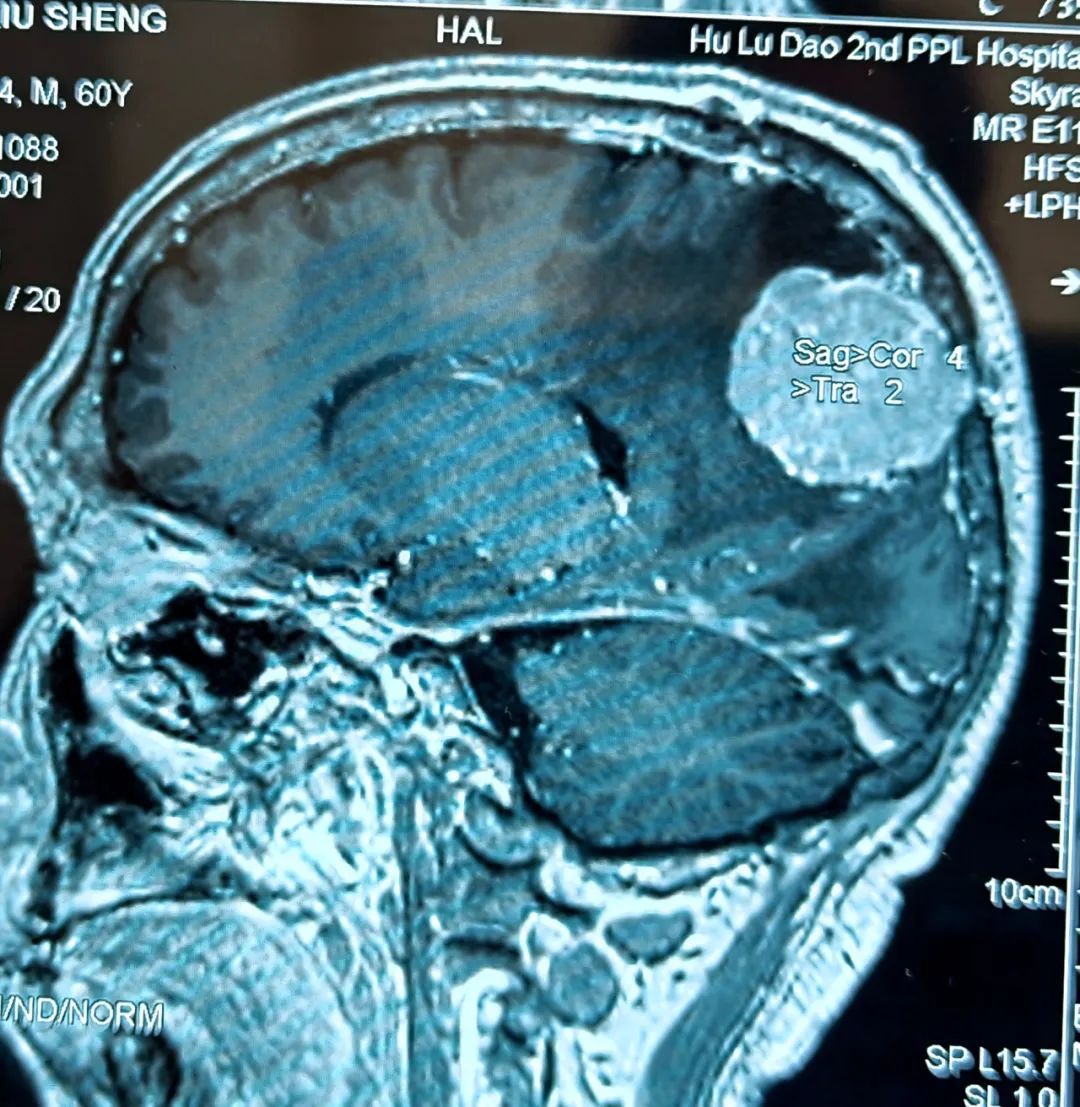

患者为60岁男性,十年前在北京某医院行右顶部矢状窦旁脑膜瘤切除术,因肿瘤侵蚀颅骨,当时切除肿瘤后同时给予部分颅骨切除一期颅骨修补术,病理诊断为非典型脑膜瘤,术后未行放疗,也未定期复查CT及MRI。三个半月前,患者因脑梗塞住院,检查时却意外发现脑膜瘤复发,且肿瘤最大直径已达5.2cm,属于巨大脑膜瘤。

- 患者术前核磁 -

情况紧急,神经内科立即邀请神经外科桑文渊主任会诊。桑主任经过询问患者病史、查体、阅片后,明确复发脑膜瘤的诊断,并与患者家属仔细沟通,表明肿瘤体积巨大且患者有头痛症状,需要待脑梗塞病情稳定后再次行手术切除肿瘤。经过耐心的病情剖析,家属对于手术的必要性表示理解。